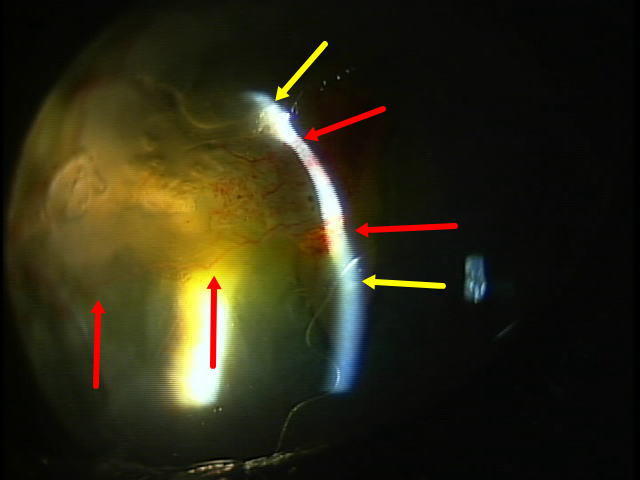

同左眼のスリットライト所見

黄色の矢印は、正常と思われる部分の角膜。赤色矢印は、変性している角膜であり光も幅が狭い。角膜が融解、薄くなっている。眼球中央部分の殆どを占拠している。